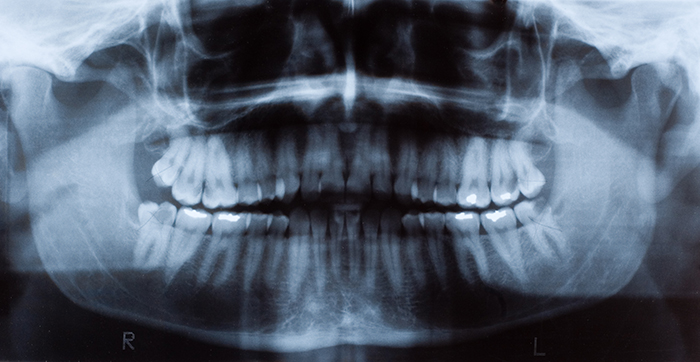

Tooth decay is the most prevalent chronic oral disease. The treatment for cavities, known medically as caries, is to remove the decayed tooth tissues and restore teeth with filling materials such as dental composites. Currently, composite restorations have a limited service life – about five to seven years -- and their replacement accounts for 60% of dental operations.

A bacterial biofilm is a slimy layer or film containing colonies of bacteria and the sticky, substance they excrete, which allows them to attach to a surface. Biofilms are more resistant than ordinary bacteria because they contain different kinds of bacteria that stick together, and the substance they excrete also forms a protective barrier around them. The biofilms on teeth are known as dental plaque. Dental plaque uses the food and drinks people consume to produce acids that break down tooth enamel leading to decay.

Dr. Xu’s group has been developing a series of novel antibacterial fluoride-releasing materials (dental composites, bonding agents and sealants) that have shown enhanced fluoride-releasing and recharge capabilities, promising antibacterial effect, and good mechanical properties or bonding strength. This new grant will support further development of these promising materials. The researchers will test a combination of new technologies that will release antibacterial agents in response to the presence of acids. These materials may also be used in sealants, crowns and cement, as well as other dental applications.